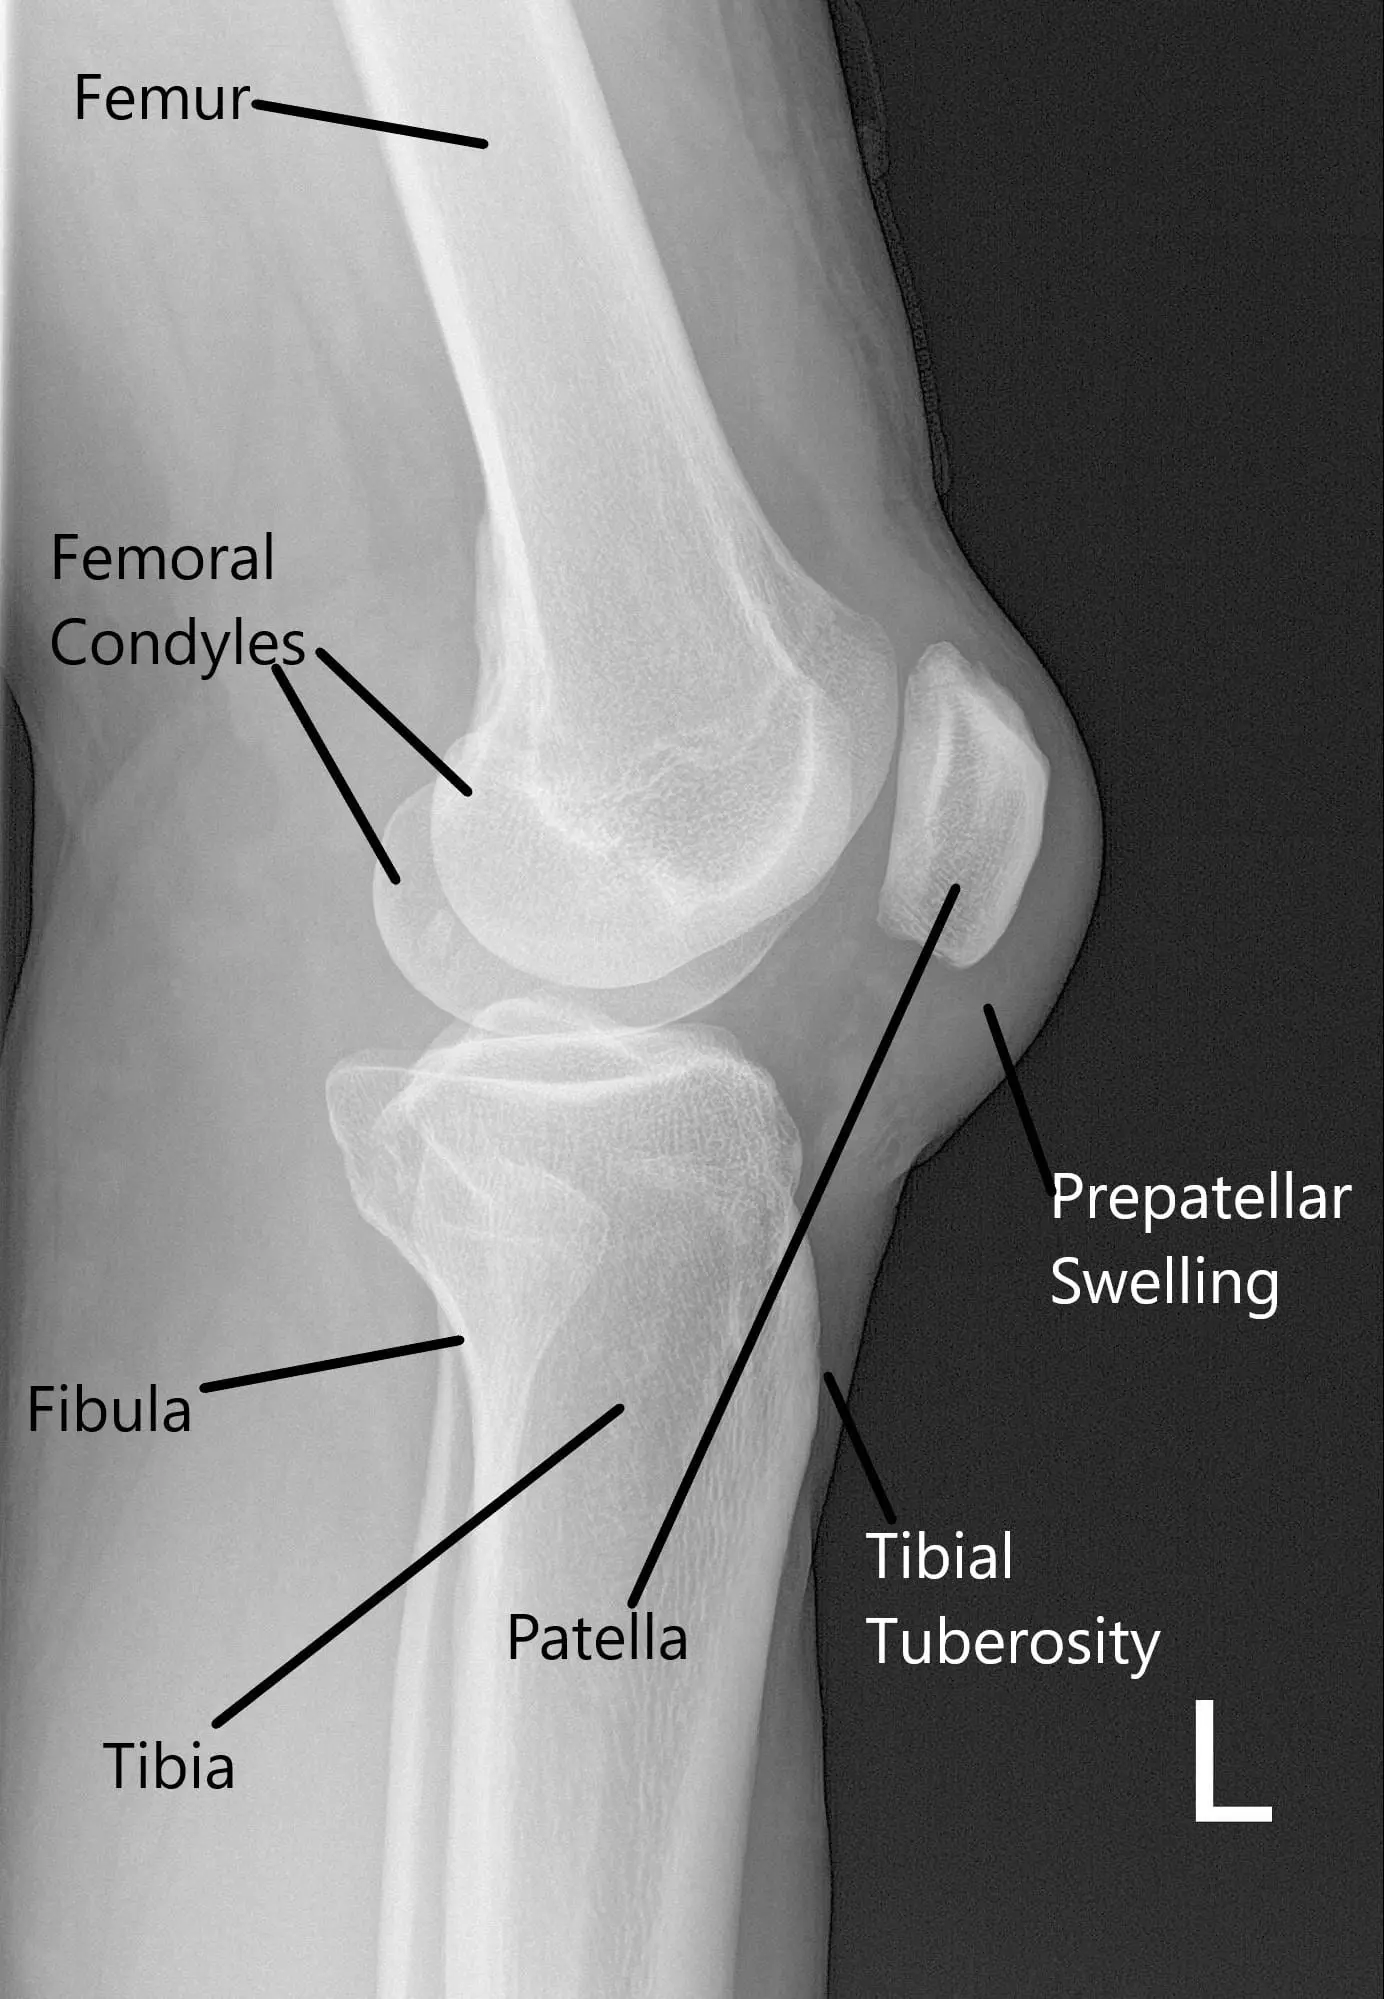

X-ray of the left knee suggested a soft tissue swelling anterior to the patella and patellar tilt.

X-ray of the left knee in lateral view.